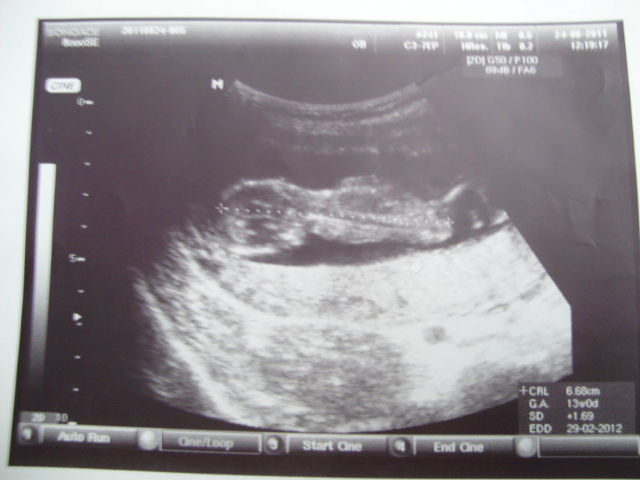

Первый Скрининг

Всё прошло отлично!Малыш активный,прыгает,плавает, скрещивает ножки,видно было даже пальчики на ногах))) Такой классный....155 ударов в минуту...я плакала от счастья и не могла ничего понять,неужели это наше второе чудо!!! Они такие разные с дочкой,это не похож на неё,совсем другой,курносенький,даже двигается по другому.Почему-то кажется,что тоже девочка))

А это фото для сравнения в первую беременность АЛЕНКА)))

Аленка-это что-то с чем-то! Она на всех УЗИ прыгала словно на скакалке,и в животе "звездочку" делала))) И родилась "электровеник"))) Этот другой!

О как классно видно! У Аленки ножки выправлены аж!))) Поздравляю! Это счастье!

Спасибо! Да, Аленка не сгибала ноги как этот.Она прыгала, а этот вертелся как "курочка гриль"